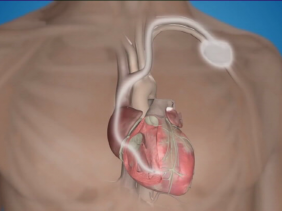

Les maladies cardiovasculaires sont une des principales causes de décès à Maurice. En 2021, 2 mille 772 décès étaient liés à ces maladies, représentant 21,3 % du taux de mortalité dans le pays. À noter aussi qu’une moyenne de quatre opérations à cœur ouvert est effectuée chaque jour au Cardiac Centre de Pamplemousses. Ce jeudi 29 septembre, nous célébrons la Journée mondiale du cœur sous le thème «utilisé le cœur pour chaque cœur ». L’occasion pour nous de réfléchir à l’importance de notre cœur.ws.com/september/